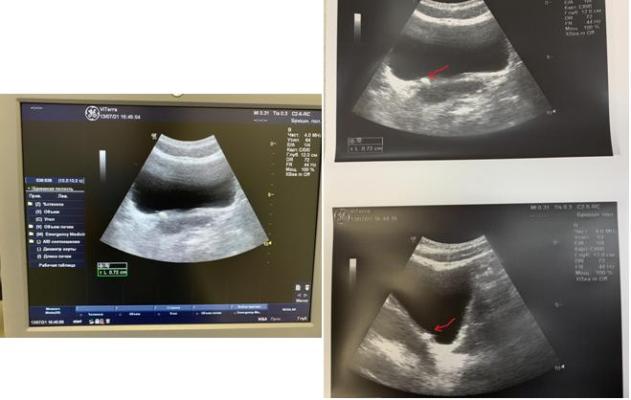

По УЗИ - правосторонняя пиелоэктазия, умеренная уретероэктазия в в\3 справа. Умеренные диффузные изменения, увеличение размеров предстательной железы.

По УЗИ - конкремент размером 6 мм визуализируется в н\3 правого мочеточника.

По результатам контрольного обследования: ОАМ, ОАК, б\х показатели - в норме, по УЗИ - конкрементов в почках и мочевом пузыре нет.